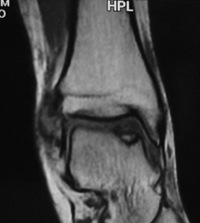

Es una lesión que afecta el hueso y el cartílago de cualquier superficie articular. Anteriormente se conocía como osteocondritis disecante. Esta lesión altera el funcionamiento normal de las articulaciones y puede producir dolor. El tobillo es una de las articulaciones que más se afecta.

Las causas principales de las lesiones osteocondrales de tobillo son los traumatismos y las alteraciones vasculares. El primer consejo que damos a nuestros pacientes es realizar descarga, controlar la sobrecarga ponderal, antinflamatorios no esteroideos (AINE) y utilizar plantillas si existe alguna alteración estructural.

El tratamiento dependerá del tamaño y localización de la lesión. La técnica más utilizada para tratar estas lesiones son las microfracturas y perforaciones realizadas con artroscopia. Cuando la artroscopia ha sido inefectiva o la lesión es muy grande, será necesario utilizar injertos, matriz cartilaginosa o cultivos de condrocitos. Nuestro equipo le aconsejará la operación que mejor se adapta a sus necesidades.